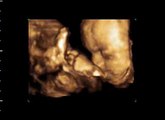

22.SSW Ultraschall Outing Mädchen, Hand und Fuss